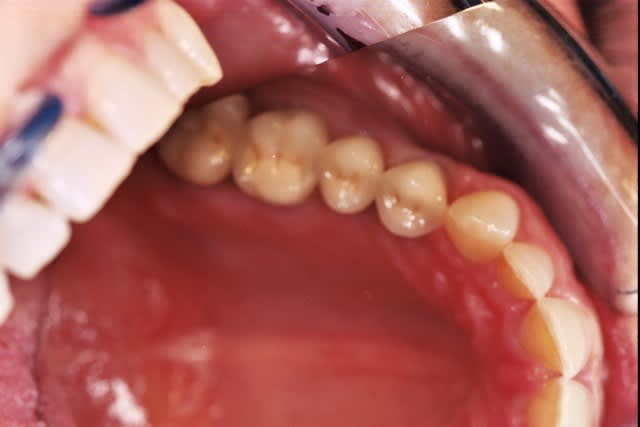

Greffe ? Expansion ?

Vos avis ?

Je suis de l'école greffe...(menton, ramus)

Expansion possible ?

Je pense virer les 35 et 45, et placer 2 implants par côté.

35 et 45 mobiles et sensibles (racines exposées)

Si on revenait à mon cas clinique...mandibule et non maxillaire, avec crêtes très fines, corticales. (zut, le scan est resté au cabinet). Faire une expansion pour une 24, c'est quand même plus facile.